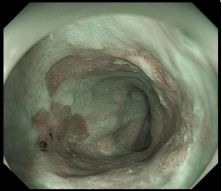

图示:食管早癌在内镜下NBI观察呈片状褐色改变,ME-NBI观察,微血管扭曲、紊乱